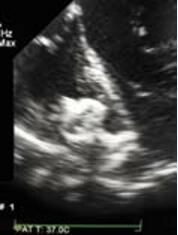

下一个让笔者思考这种手术的病例是一个纤维瘤完全遮盖了右室分流侧的室间隔缺损患者(图10-7)。已经完成大量的室间隔缺损心内直视手术,因此笔者们对于隔瓣和残存膜部室间隔由于无菌性炎症刺激形成的这种结构非常熟悉。此时没有任何可能通过直接的右室穿刺穿过缺损。而且,通过右房途径也无法完成。缺损的血流直接吹向三尖瓣,但是有时候也可能以极度弯曲的角度朝向流出道部进入小梁区。但是,缺损在膜性结构下方,封堵器压在膜性区域理论上是安全的。因此笔者用一个穿刺针在缺损轴线方向(中部)精确的穿刺了膜性结构,随后自由通过导丝、输送系统,成功封闭了该“复杂”缺损(图10-8)。在某些病例采用本方法时,非常重要的一点是穿刺针顶端对准目的穿刺点。为了达到此目的,穿刺针对准膜,获得最佳超声图像,仔细稳定住,通过不同TEE切面核查。笔者认为只要遵守一定规则,这个方法非常有效,绝对安全。纤维瘤组织的破坏也不会导致心律失常的发生。笔者已经成功完成数例此类患者,笔者很有信心,也推荐大家在一些复杂情况下可以尝试。